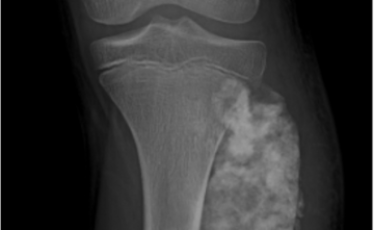

deteksi kanker tulang lebih dini dapat membantu memperbesar kemungkinan sembuh.